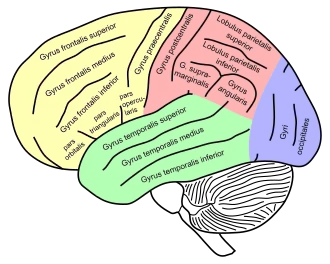

Lateral view of a human brain, main gyri labeled | |